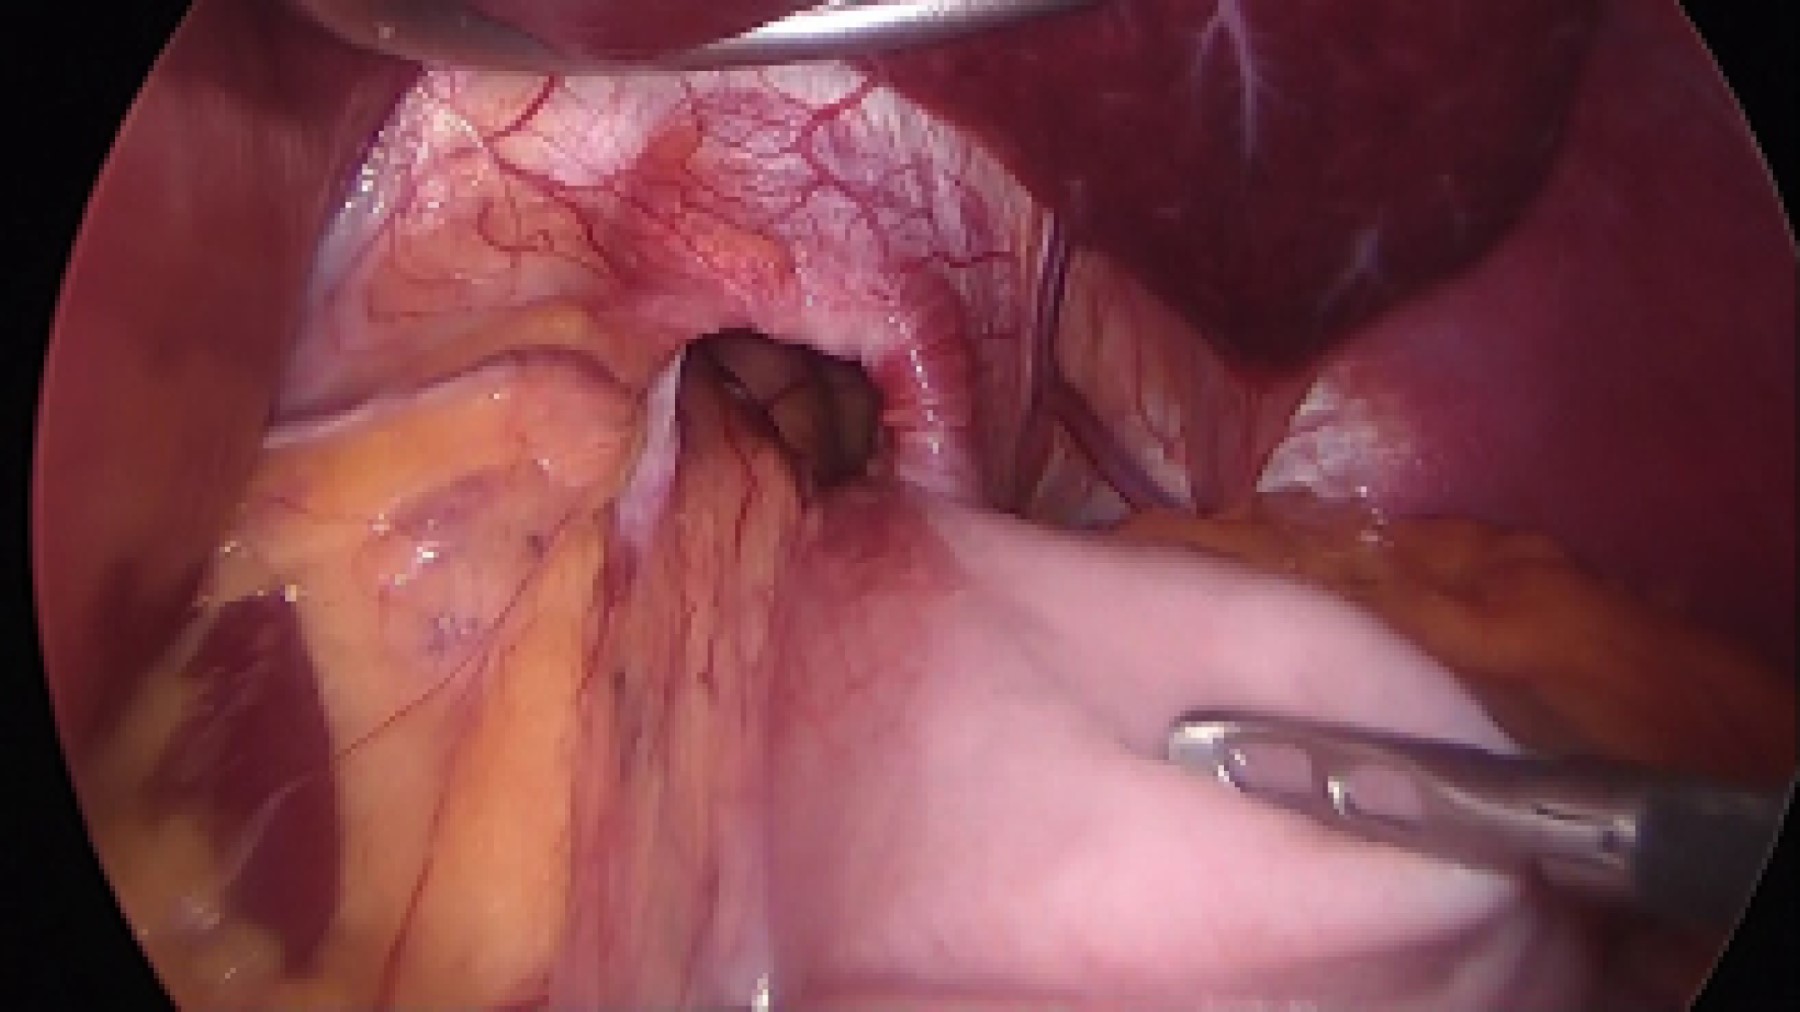

Posteriormente se realizó gastroscopía (Figura 2), teniendo como hallazgos hernia hiatal tipo III y vólvulo gástrico sin compromiso vascular aparente. Presentó incapacidad de colocación de la sonda nasogástrica (SNG) y se le indicó ayuno, solución Hartmann, protector de mucosa gástrica, antiemético y analgésicos intravenosos. Fue valorada por parte de cirugía y se programó para laparoscopía diagnóstica y resolución quirúrgica del vólvulo.

Técnica quirúrgica: bajo anestesia general se efectuó laparoscopía diagnóstica con colocación de cuatro puertos, separador de Nathanson, se encontró cuerpo de estómago por arriba del hiato, se procedió a la reducción del estómago del fondo gástrico y desvolvulación, se cerraron los pilares diafragmáticos con sutura prolene 2-0 llevando a cabo funduplicatura parcial tipo Toupet con calibración por endoscopía transoperatoria de 60 French con dos puntos para fijación del labio derecho de la funduplicatura y un punto del labio izquierdo hacia los pilares, se corroboró la confección de la funduplicatura con endoscopía, además de gastropexia a la pared abdominal anterior con sutura prolene 2-0. No hubo complicaciones (Figuras 3 y 4) y se finalizó evento quirúrgico. El posoperatorio inmediato fue en cuidados intermedios para vigilancia por riesgo de complicaciones.